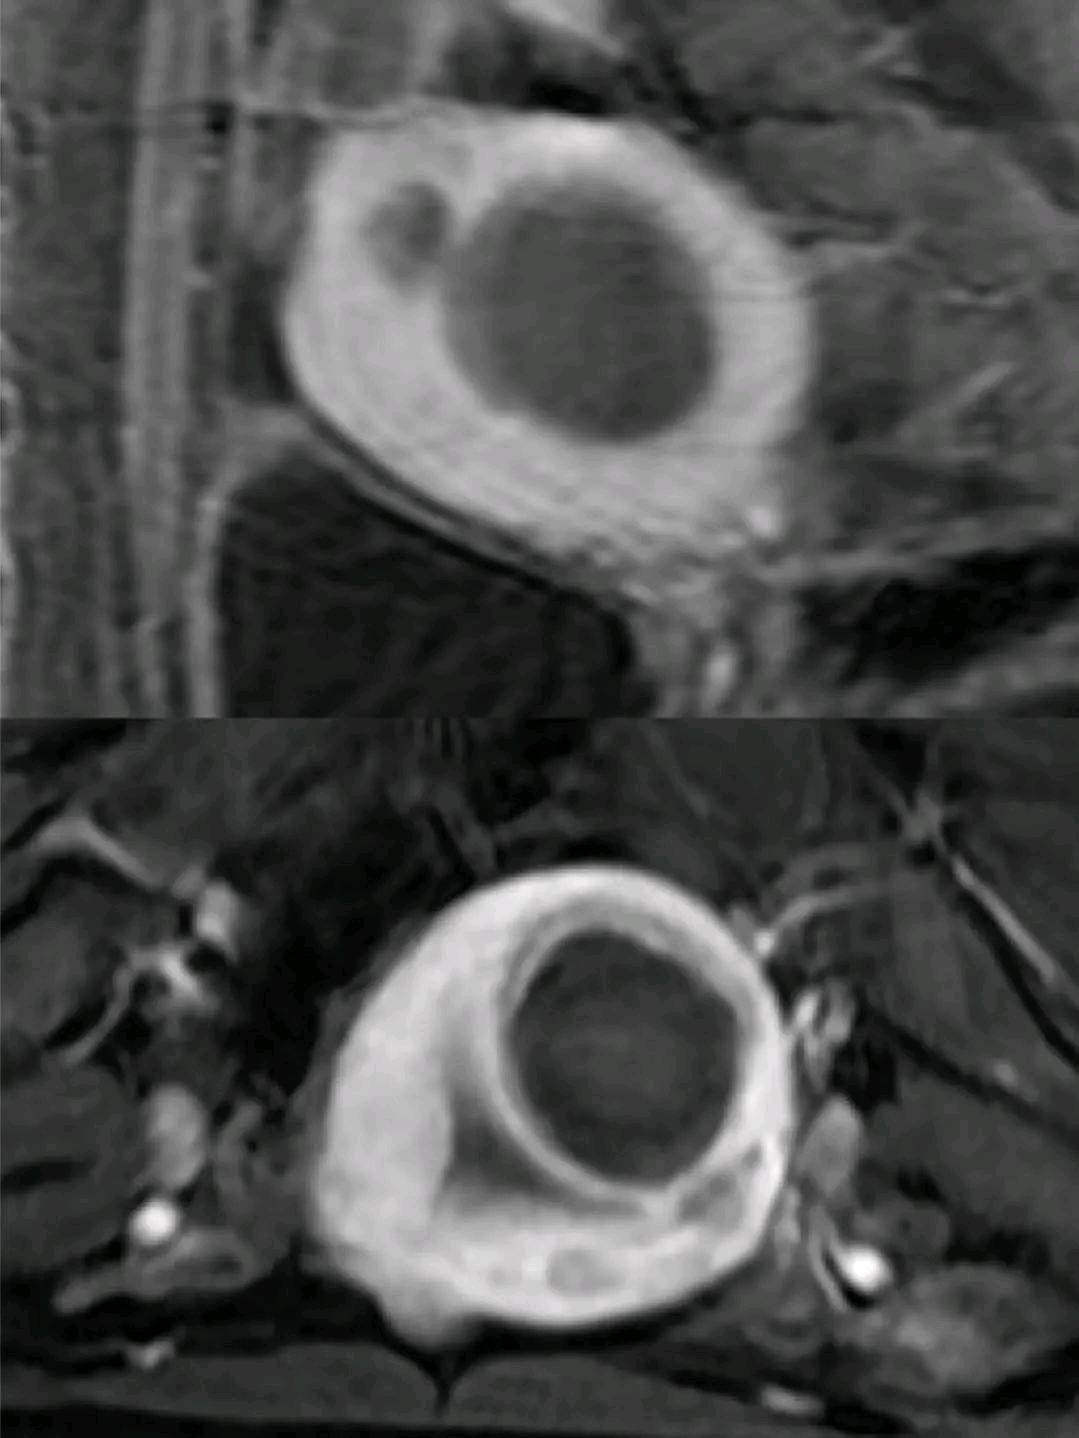

上图是我们一个子宫肌瘤的患者磁波治疗术后复查的MRI图像,这个患者在术后1年左右怀孕,计划分娩的时候问我是否可以顺产,你可以图片里面可以看出来,黑影的坏死部分局限于子宫肌瘤的内部,而周边的子宫内膜和肌层均保留完好,这样的子宫自然分娩没有问题,当然产科一些指征需要剖宫产的另当别论。